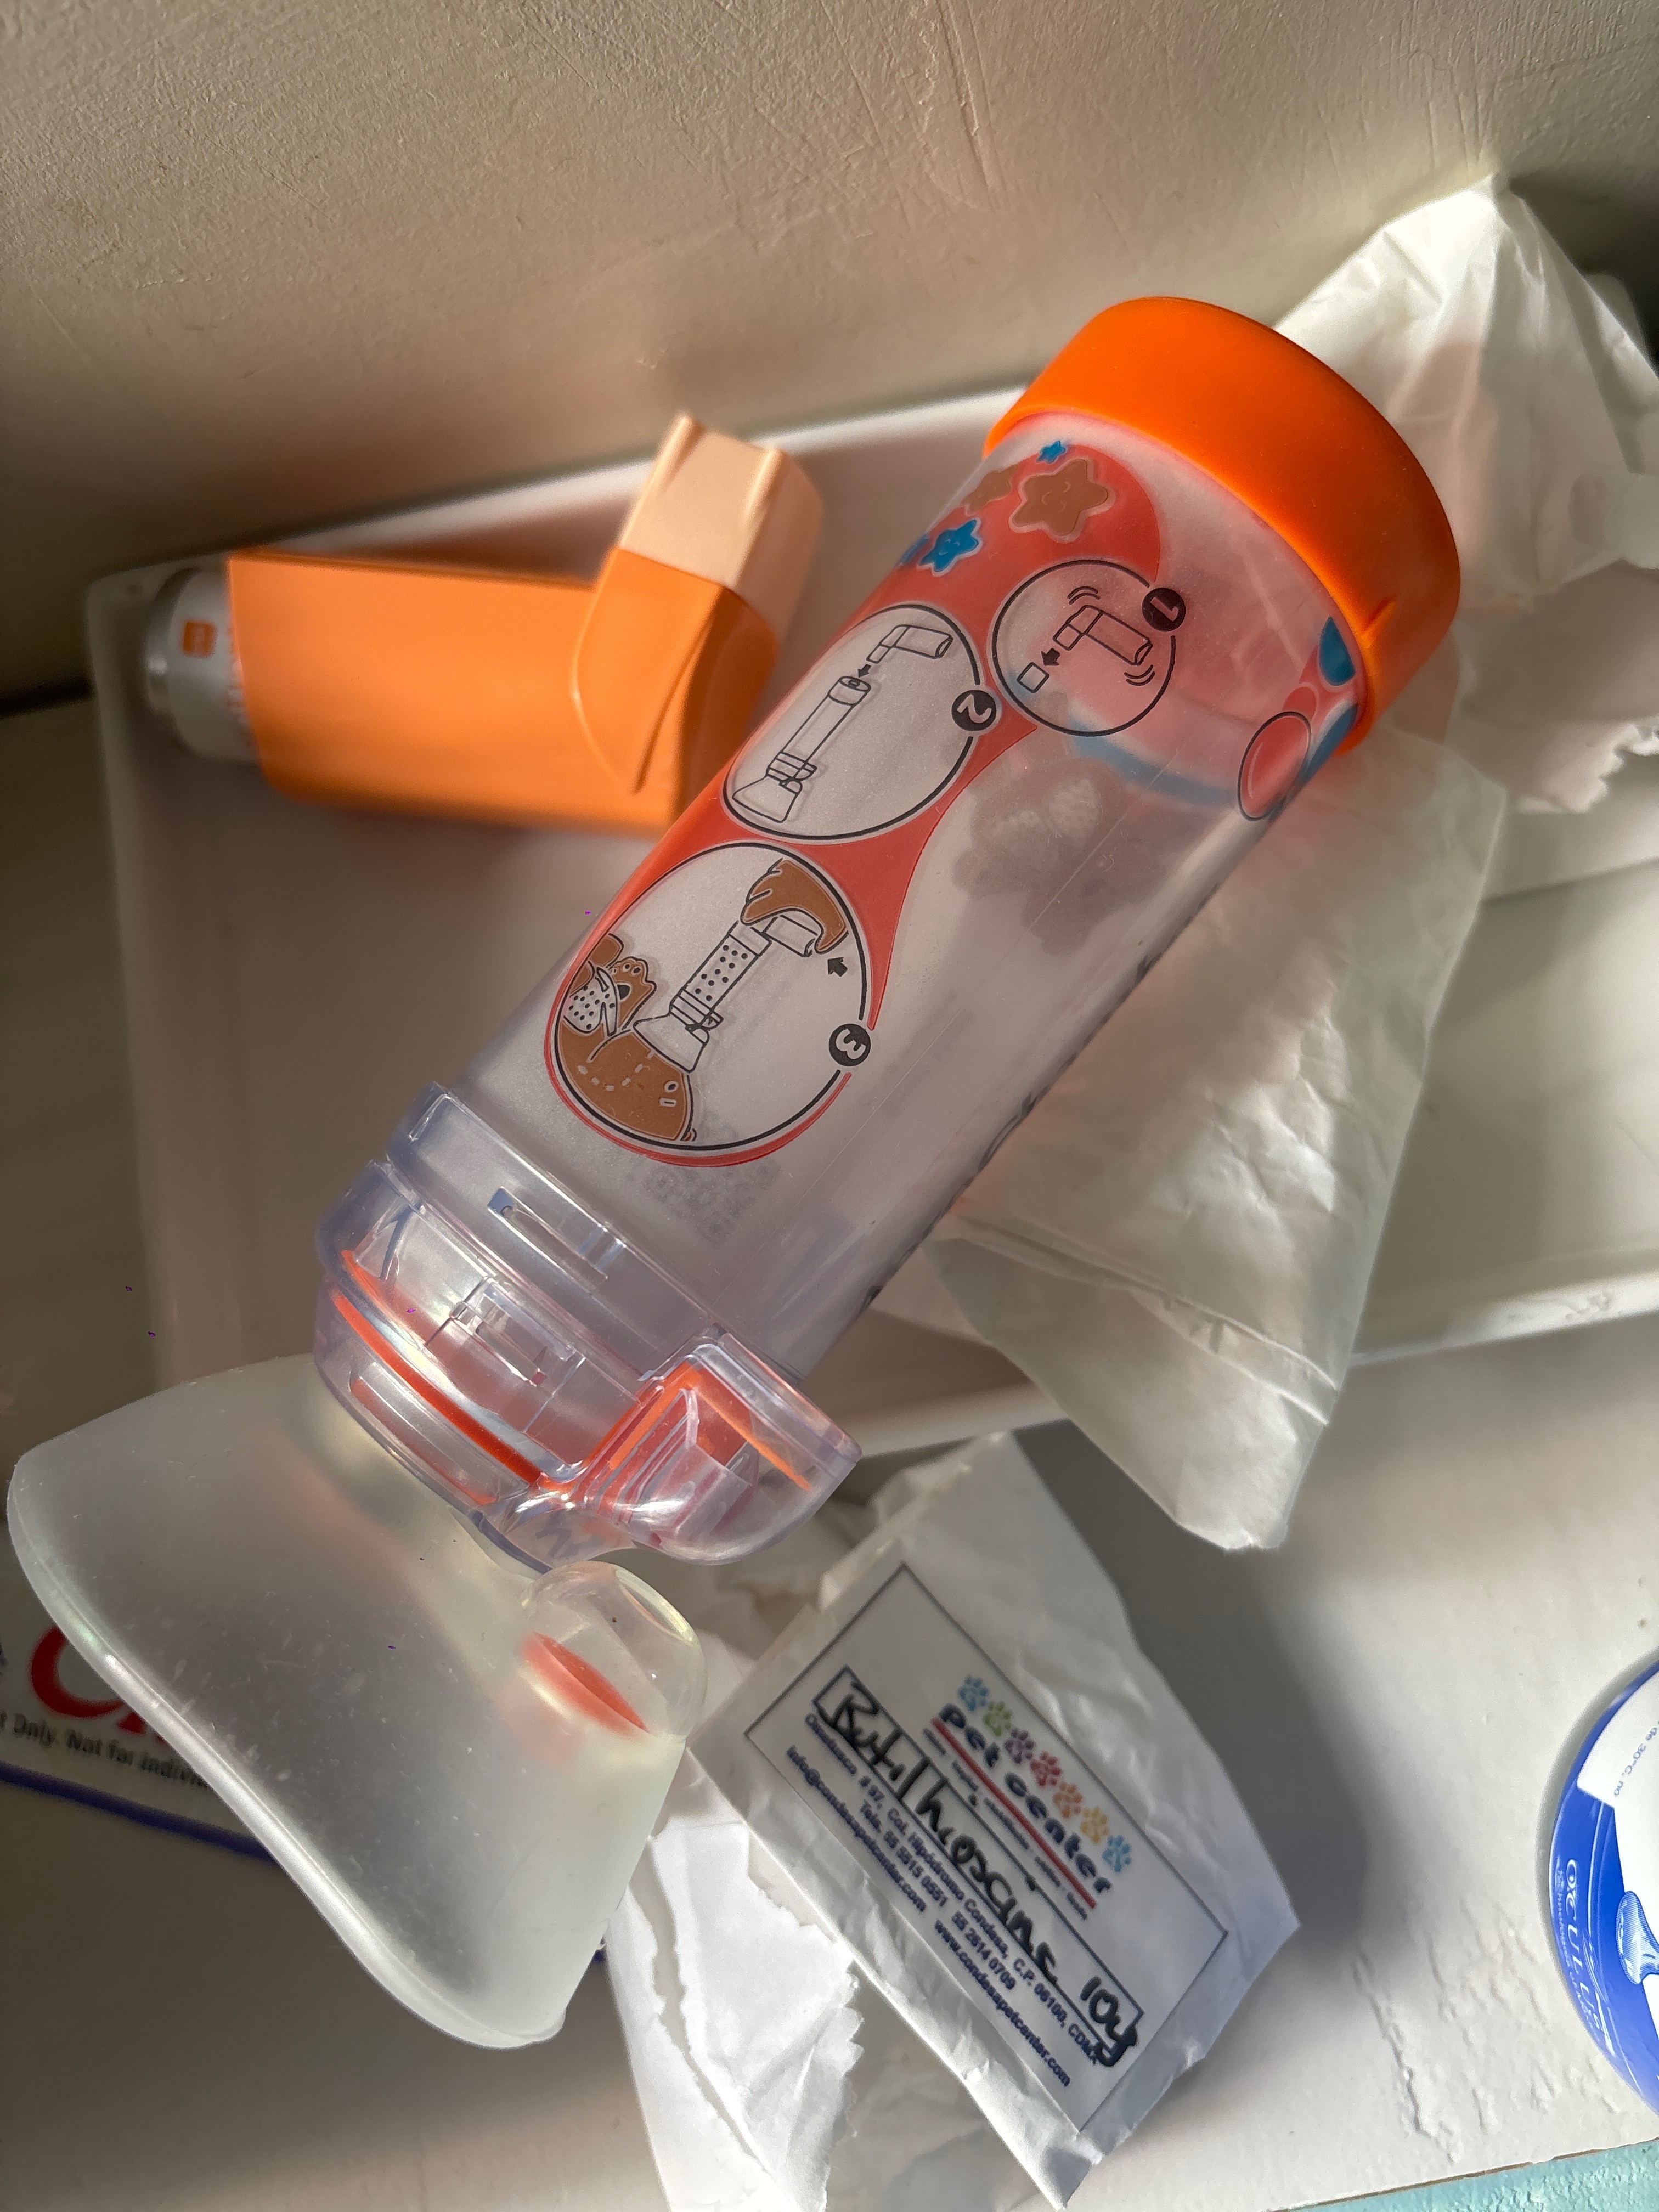

Es un gatito muy feliz, muy joven tiene aproximadamente 3 años, el estaba super sano pero hace 6 meses comenzó con dificultades para respirar su diagnostico es (Asma Felino Crónico)

Es de por vida, el tema es que lo he llevado a miles de veterinarios y ninguno me ha podido ayudar y cada vez su salud empeora por no darle un tratamiento correcto.

Tienen que someterlo a una operación con sedación, estudios para poderle hacer una tomografía y de ahi sacar estudios o resultados de lo que puede tener para encontrar un tratamiento ideal para el y que logre tener una vida lo más normal posible.